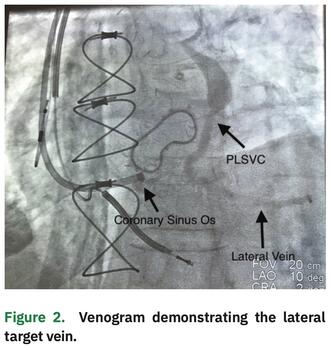

Subsequently, we attempted to selectively engage the CS ostium; however, an obstruction was encountered. An inner catheter was then used to partially engage the coronary sinus ostium, although the CS sheath could not be advanced. Angiography, via the CS sheath, revealed a subtotal occlusion and retrograde flow through what appeared to be a remnant vein of Marshall, but with a connection to the left innominate vein, consistent with a small PLSVC (Figure 2). Due to the CS ostial stenosis, the vein of Marshall or PLSVC provided venous return of the heart via its connection to the left innominate vein.

Given the subtotal occlusion, it was decided to abandon any further attempts of placement of the CS lead through the ostium. Rather, we proceeded with placement of the CS lead using the PLSVC. The previous venogram (Figure 1) demonstrated a medium to large caliber lateral vein without significant branching, which could be targeted with a quadripolar LV pacing lead. The inner catheter was utilized to subselect the PLSVC and deliver the lead into the lateral vein, which resulted in a stable lead position with adequate pacing and sensing characteristics. The greatest stability was achieved with the distal lead location within this vein. This site also provided an excellent pacing complex without diaphragmatic stimulation (Figure 4).